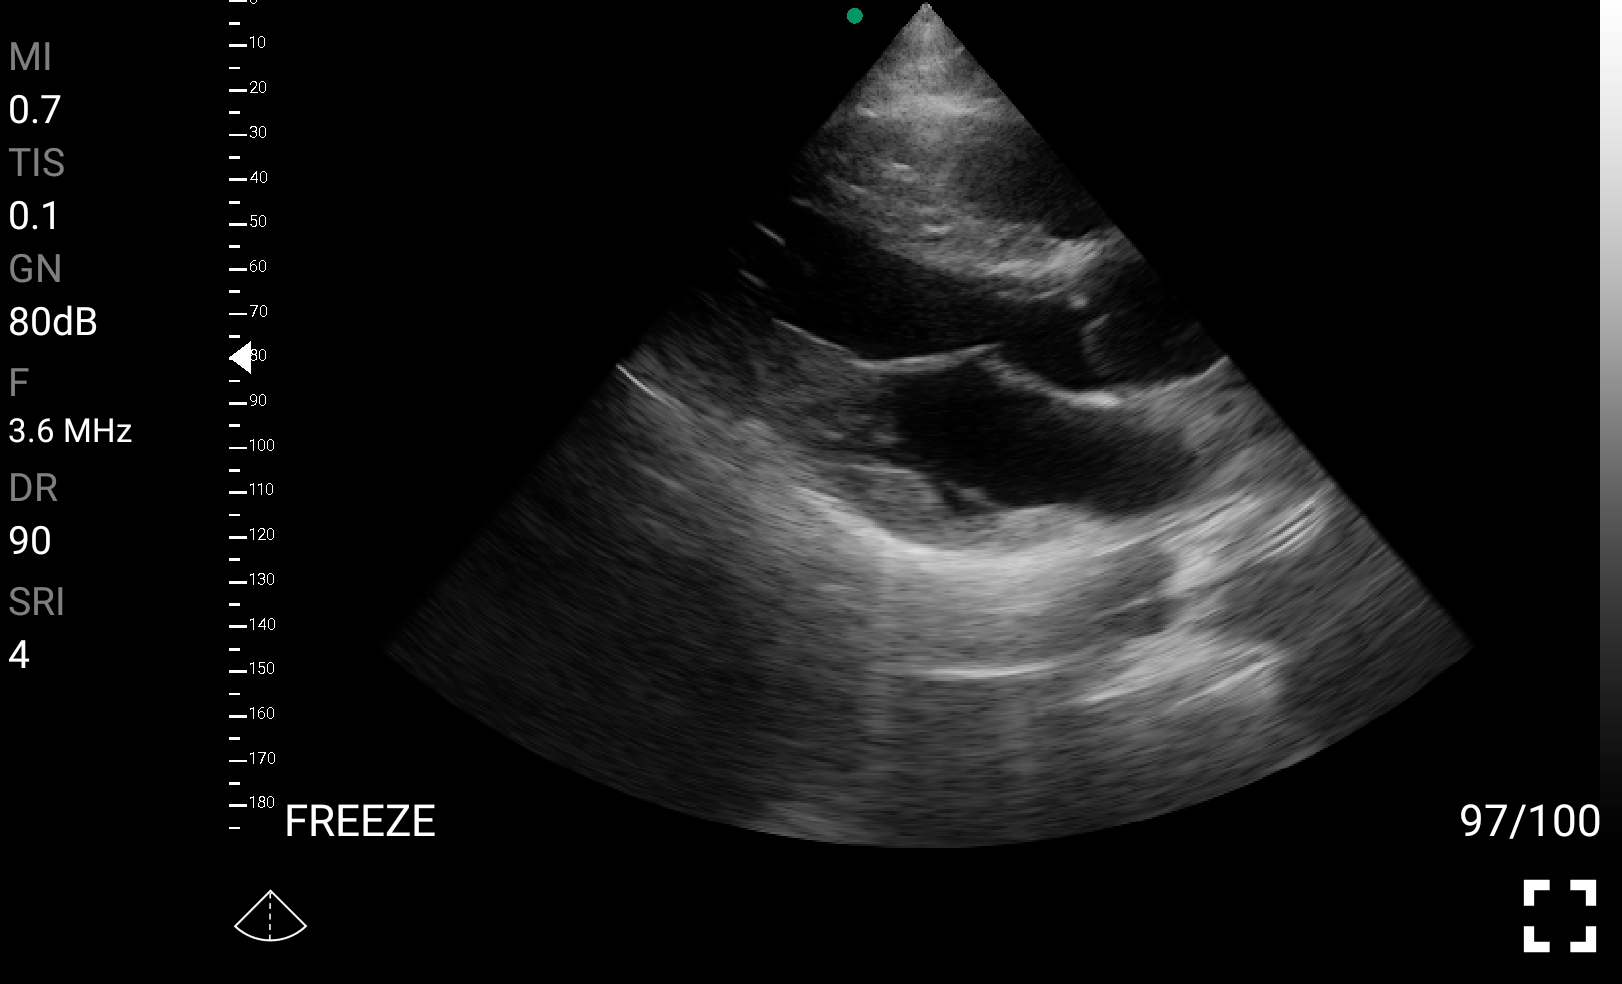

Παραδείγματα

Ολες οι παραπάνω απεικονιστικές εξετάσεις έχουν ληφθεί από φορητή συσκευή όπως: Apple Iphone, Tablet, Samsung Mobile Phones και διάφορες άλλες φορητές συσκευές.

• Echocardiography: Ταχεία εκτίμηση της καρδιακής λειτουργίας σε ασθενείς με υπόταση ή ανακοπή.

Παραδείγματα Video